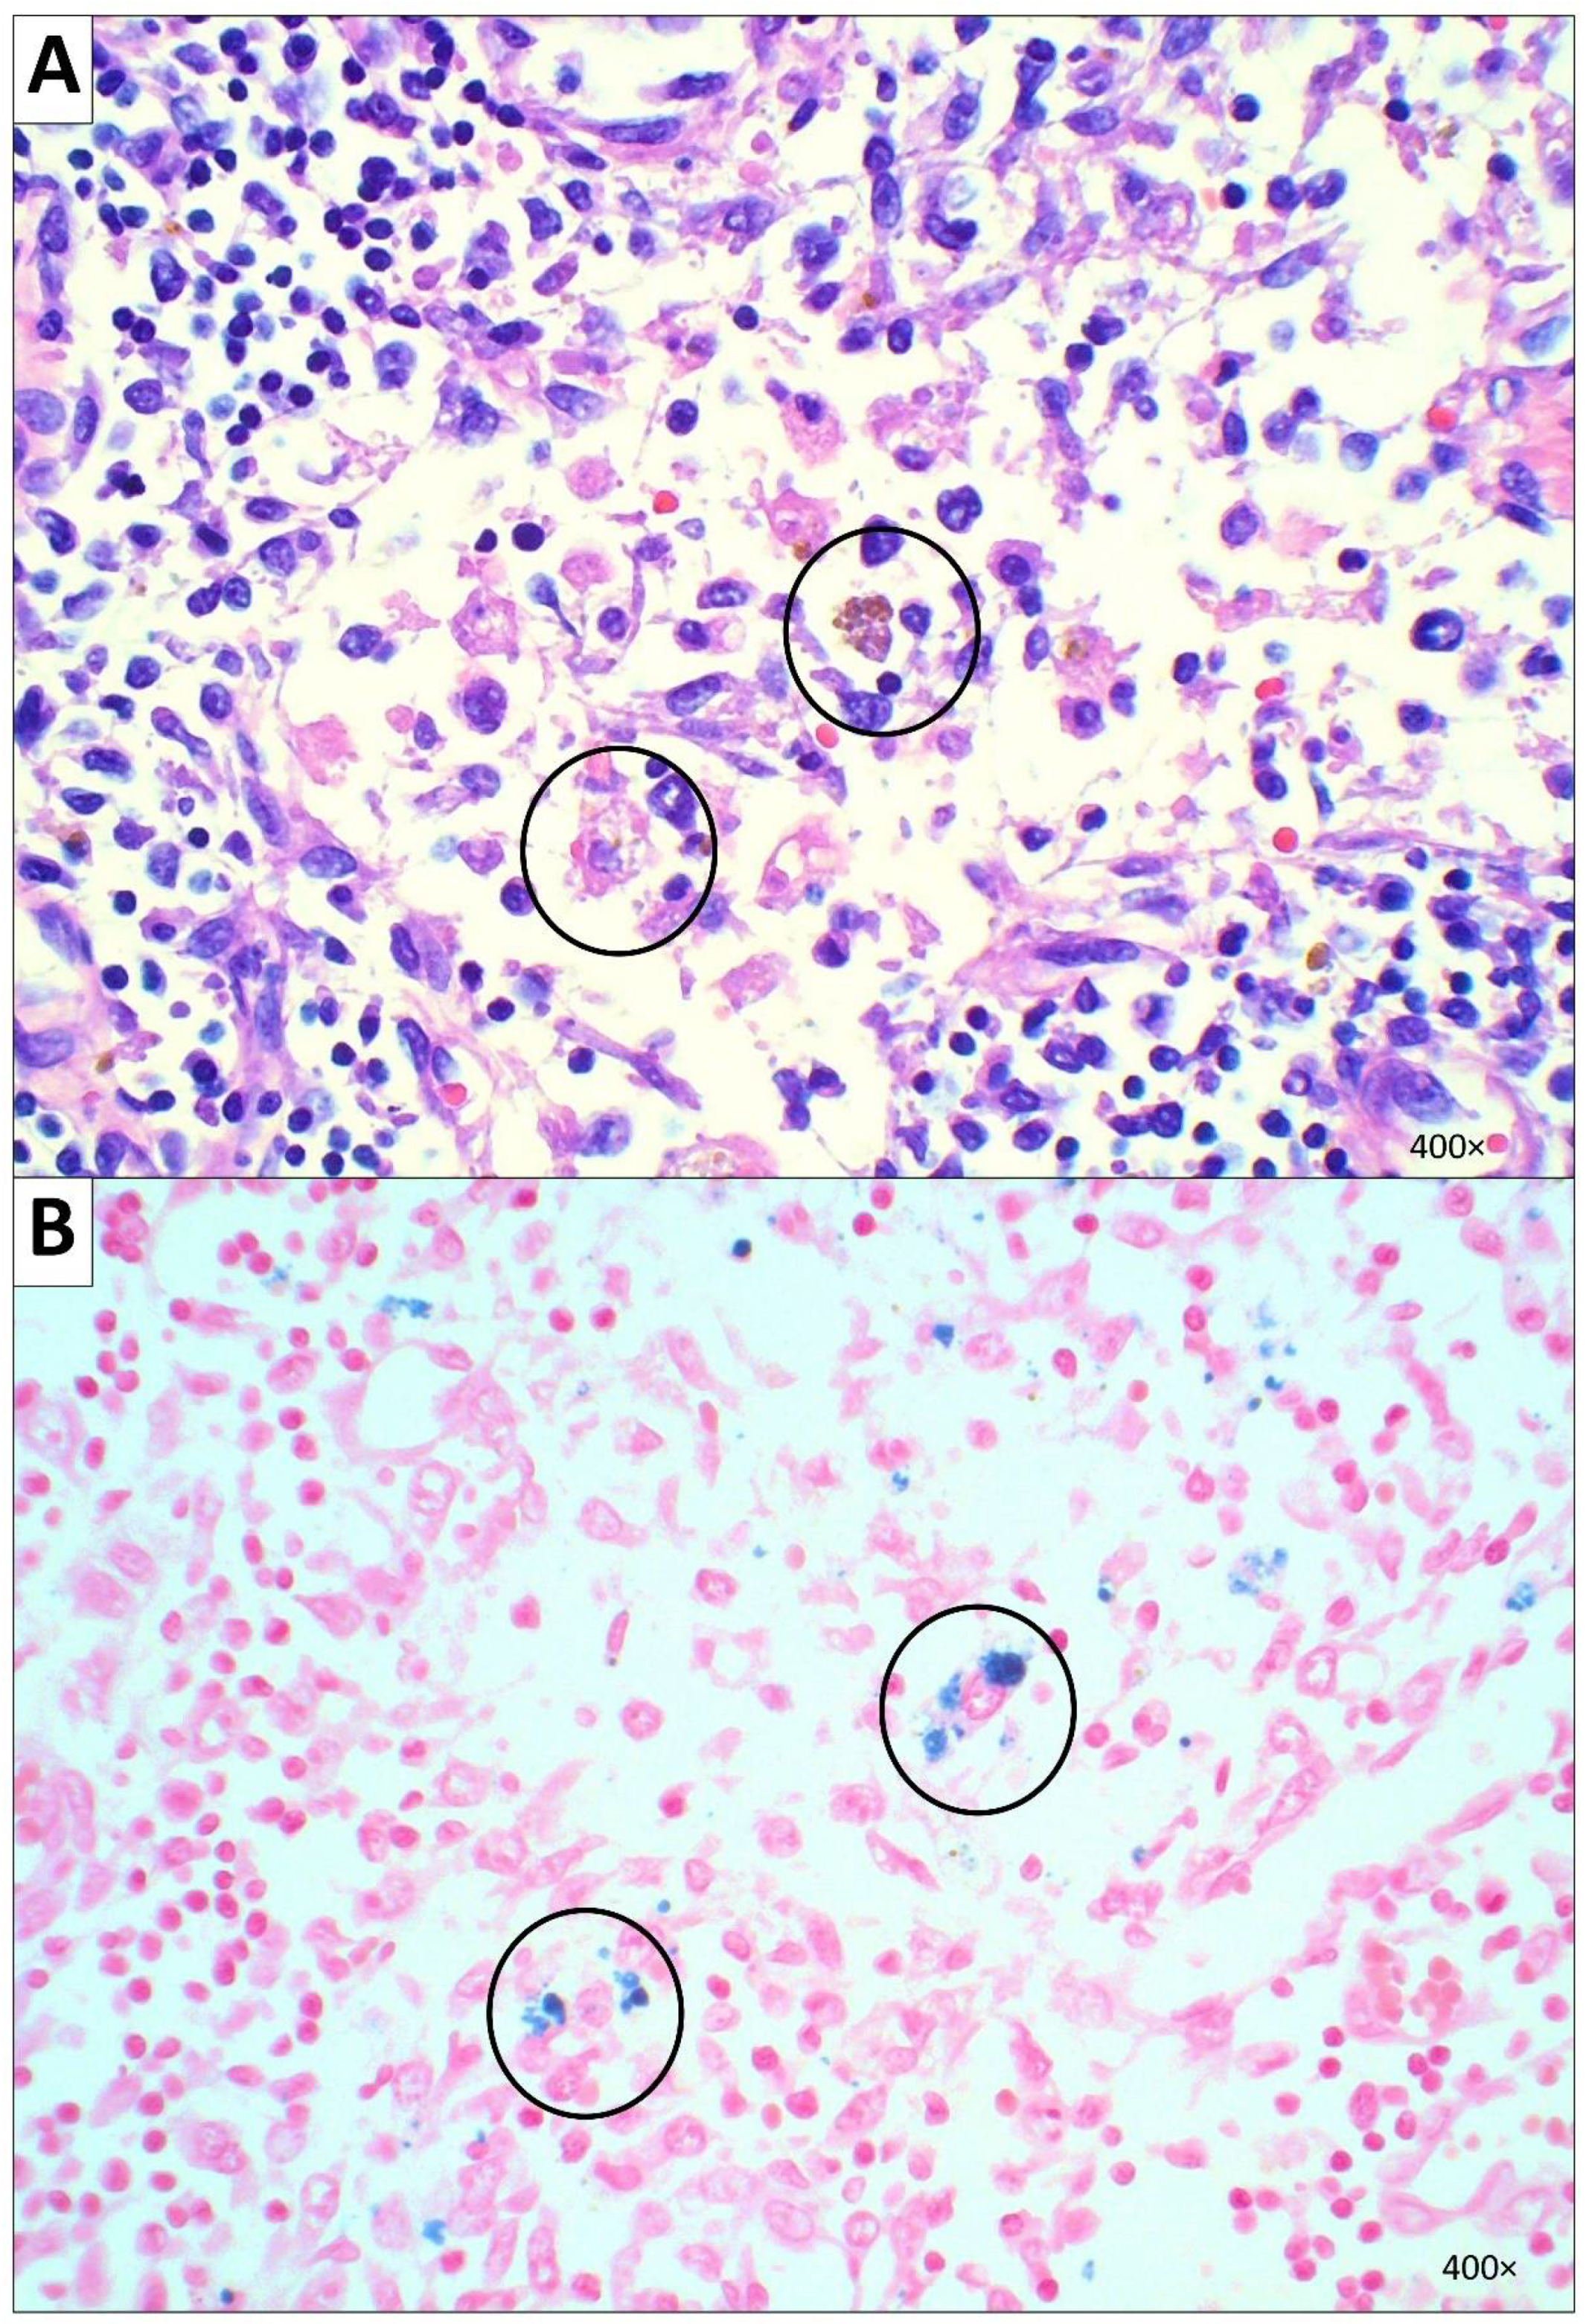

2.2.5. Hematopoietic System